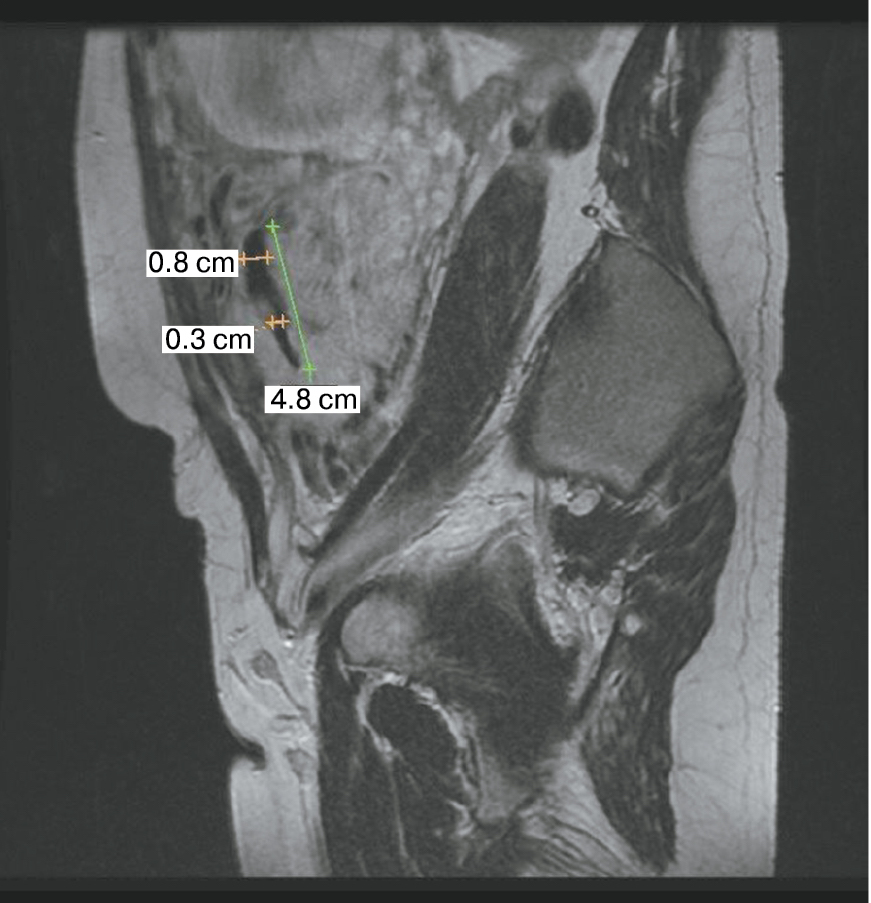

Также стоит выделить особый тип плацентарной гиперваскуляризации, а именно включение в плацентарной ткани изменений по типу «обнаженного сосуда» (рис. 1, 2). Мы провели анализ встречаемости данного признака среди наших пациентов. Любопытным наблюдением явилось то, что данный симптом в нашей выборке встречался только при наличии placenta percreta – 6 случаев, а именно при поражении параметриев, и не встречался при плацентарной инвазии, ограниченной миометрием. «Мостовидные сосуды» были менее специфичны, тем не менее, их наличие также сопровождало тяжелые формы врастания, обусловленные более глубокой инвазией ворсин хориона, – 8 случаев.

Рис. 1. МРТ placenta percreta, симптом «обнаженного сосуда»

Рис. 2. МРТ placenta percreta, симптом «обнаженного сосуда»

Дополнительный интерес в прогностическом плане вызывает симптом «обнаженного сосуда», представляющий собой хотя бы 1 линейную структуру диметром 5 мм и длиной около 2 см. Сама по себе гиперваскуляризация – признак при МРТ, имеющий специфичность до 80%; значения чувствительности колеблются от 42 до 69% [14]. При макроскопическом исследовании выявляется сеть субхорионических ветвистых стволовых сосудистых структур диаметром 3–5 мм, длиной 2–8 см [15]. Свое название они получили ввиду того, что минимально окружены тканями хориона и, проникая через толщу плаценты, давали минимальное количество ветвей. Dighe M. из Вашингтона опубликовала сходные данные о значимости диаметра внутриплацентарной сосудистой сети плода в прогнозе врастания плаценты; диаметр сосуда 2 мм или более часто встречался при наличии PAS, тогда как диаметр сосуда 3 мм или более был ассоциирован с более глубокой степенью инвазии и риском перипортальных кровотечений [16].